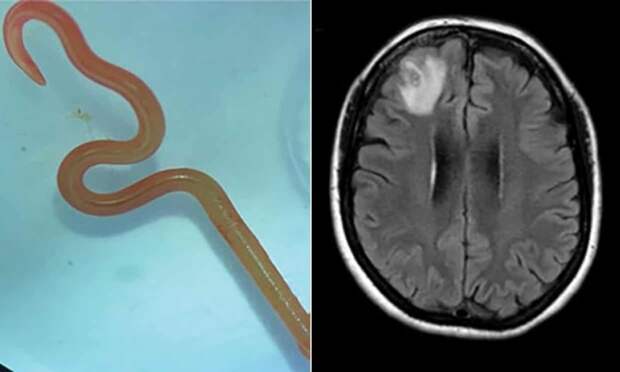

У гражданки Австралии, которая жаловалась на боли в животе, понос, а также расстройство памяти и депрессию, в мозгу был обнаружен живой 8-сантиметровый червь-паразит.

Это первый случай в истории медицины, когда данный червь обнаружен в организме человека. Обычно он паразитирует на крупных змеях и считалось, что для человека он не опасен.

Ophidascaris robertsi - круглый червь-паразит, обычно встречающийся в организме змей семейства питонов. И пациент больницы в Канберре оказался первым в мире случаем обнаружения данного паразита в человеческом теле.